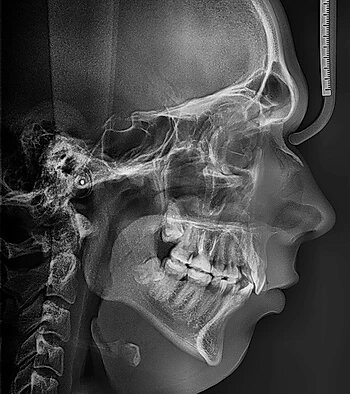

ТРГ- телерентгенограмма, стандартный 2-х мерный рентгеновский снимок, назначаемый в основном стоматологами-ортопедами, челюстно-лицевыми хирургами и травматологами.

Снимок можно произвести в двух основных проекциях, прямой и боковой, в зависимости от того, что именно хочет увидеть врач. На снимке ТРГ можно увидеть не только костную, но и мягкие ткани, что позволяет лучше составить программу лечения в ортодонтии. Для чего нужен снимок ТРГ: - определить правильность расположения верхней и нижней челюсти - определить наклон зубов относительно основания черепа

- оценить мягкие и костные ткани лица- определить наличие асимметрии лицевой части черепа - определить состояние прикуса и наличие его нарушений